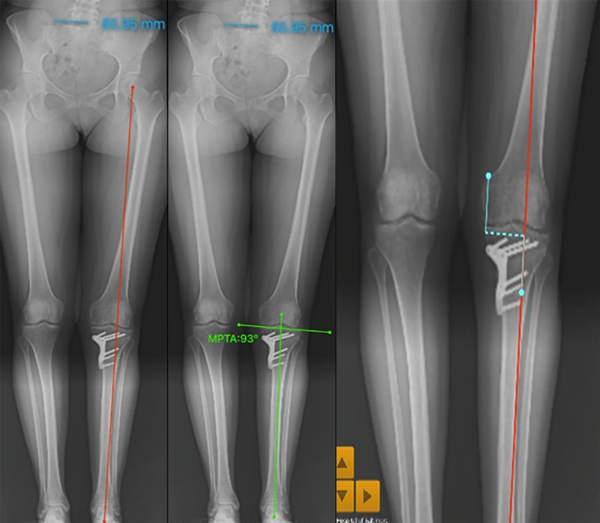

Resultados postoperatorios

La radiografía panorámica postoperatoria se observa en la línea de carga del miembro inferior izquierdo, que pasa por el 62% del ancho de los platillos tibiales, ubicada a 45 mm, desde el platillo medial.

Con el software se corrobora esta medida, comprobando la exactitud del método de planeamiento y su resultado, también el MPTA resultante de 93°, que es exactamente el mismo calculado en el planeamiento (fig. 30).

Figura 30: Resultados postoperatorios.